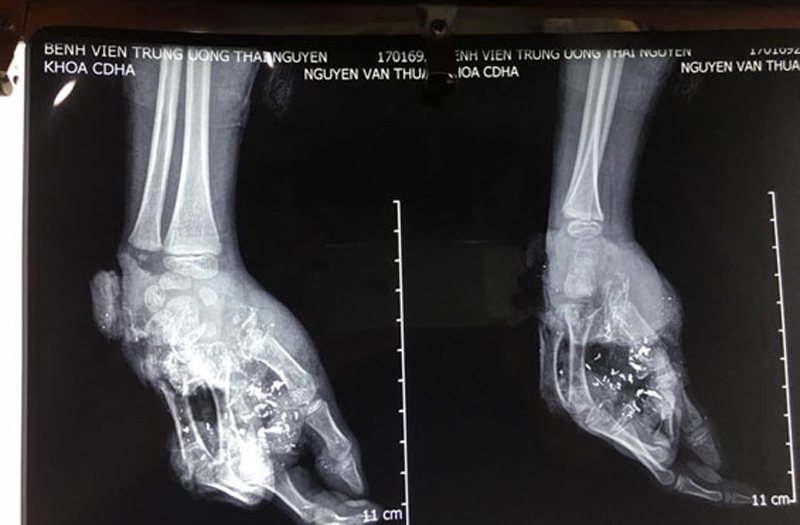

Tại BV TƯ Thái Nguyên, cháu Thuận đã được kíp mổ do bác sĩ Nguyễn Thanh Tùng và bác sĩ Phạm Ngọc Tuấn Anh, Khoa Chấn thương Chỉnh hình loại bỏ toàn bộ các phần ngón tay dập nát, nối gân, nối mạch máu bảo toàn ngón cái và ngón trỏ. Đến sáng 24/1, hai ngón tay được bảo toàn đã hồng hào và có biểu hiện tiến triển tốt.

Trao đổi với chúng tôi, bác sĩ Nguyễn Thanh Tùng cho biết, quả pin phát nổ đã gây tổn thương nghiêm trọng. Bàn tay phải của Thuận mất toàn bộ xương bàn ngón giữa, áp út và ngón út; mất toàn bộ bờ ngoài bàn tay; tổn thương toàn bộ hệ thống gân bàn tay, xương bàn tay và gân cơ. Ngoài ra, khu vực lòng bàn tay có nhiều dị vật mảnh vỡ bằng kim loại. Dự kiến, cháu Thuận sẽ tiếp tục được phẫu thuật ít nhất 1 lần nữa để chuyển vạt và ghép da vào những vết thương hở.